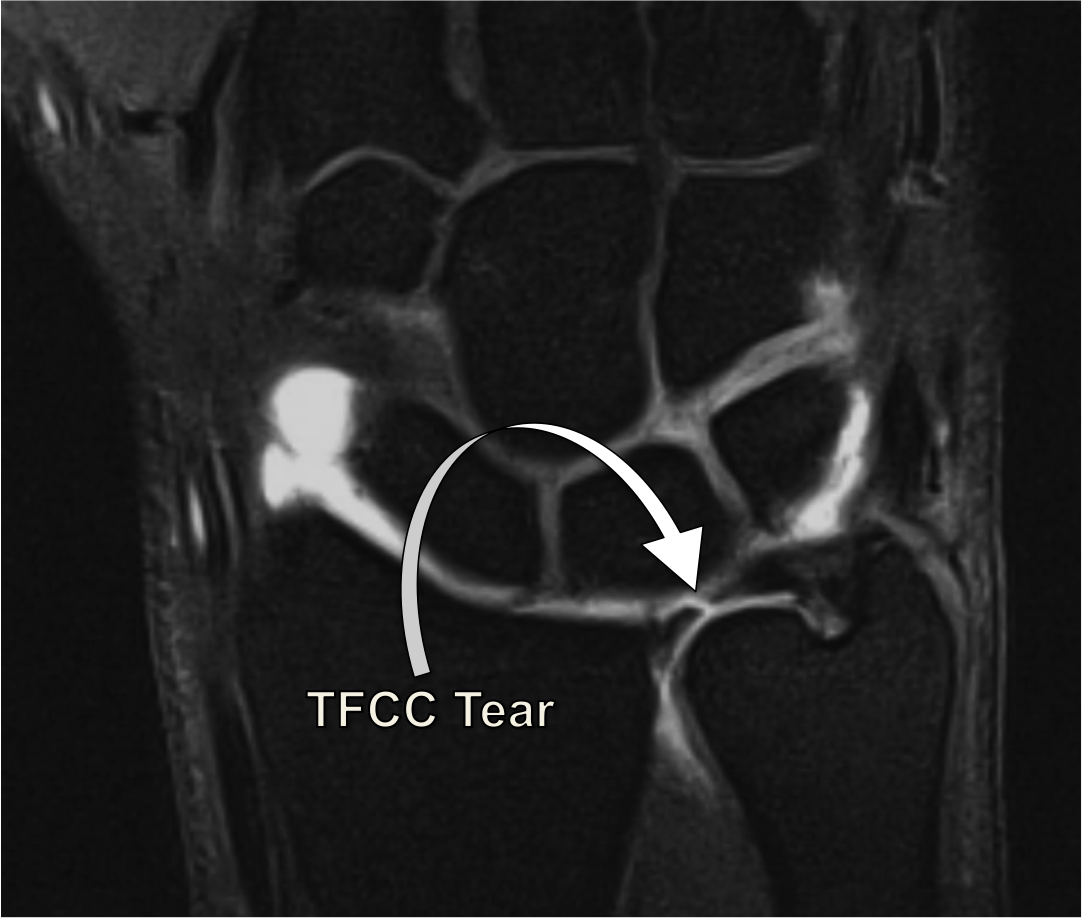

Recovery Time For Tfcc Surgery - What is the recovery time after tfcc surgery? Debridement of a tfcc central. Repair of a tfcc peripheral tear may require a cast that includes the elbow for at least 6 weeks. Recovery time varies based on the type and extent of the tear and the chosen treatment approach. Recovery typically takes 3 to 6 months, depending on the procedure and the severity of the injury.